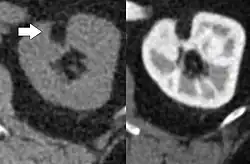

Angiomyolipoma in both kidneys (arrows) as seen on CT scan. The tumors are hypodense (dark) due to fat content.